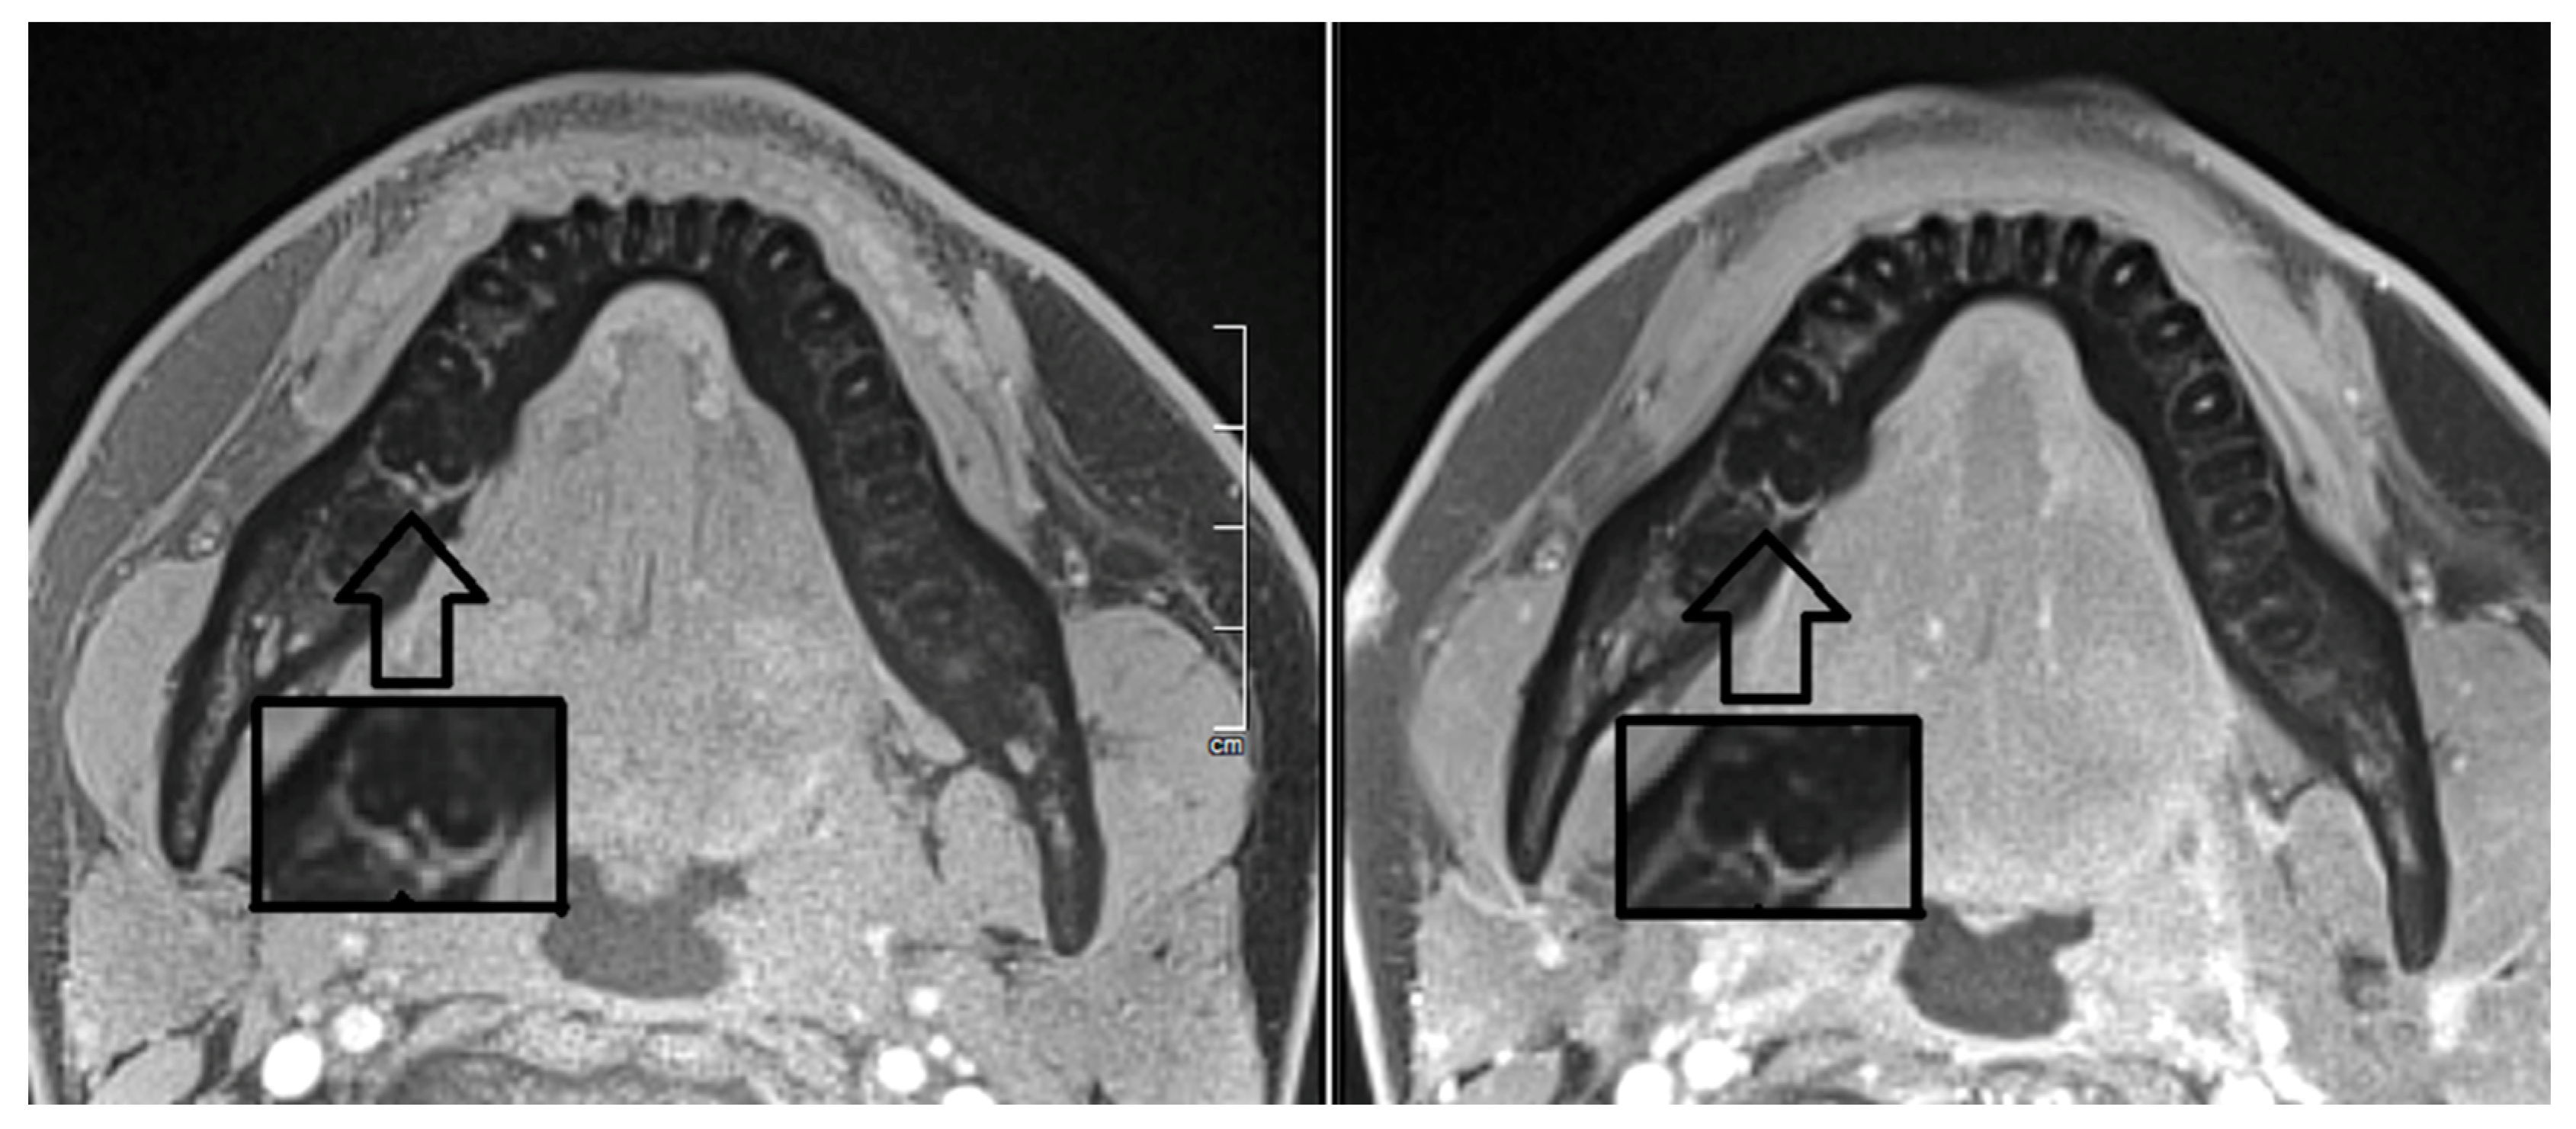

2. Report